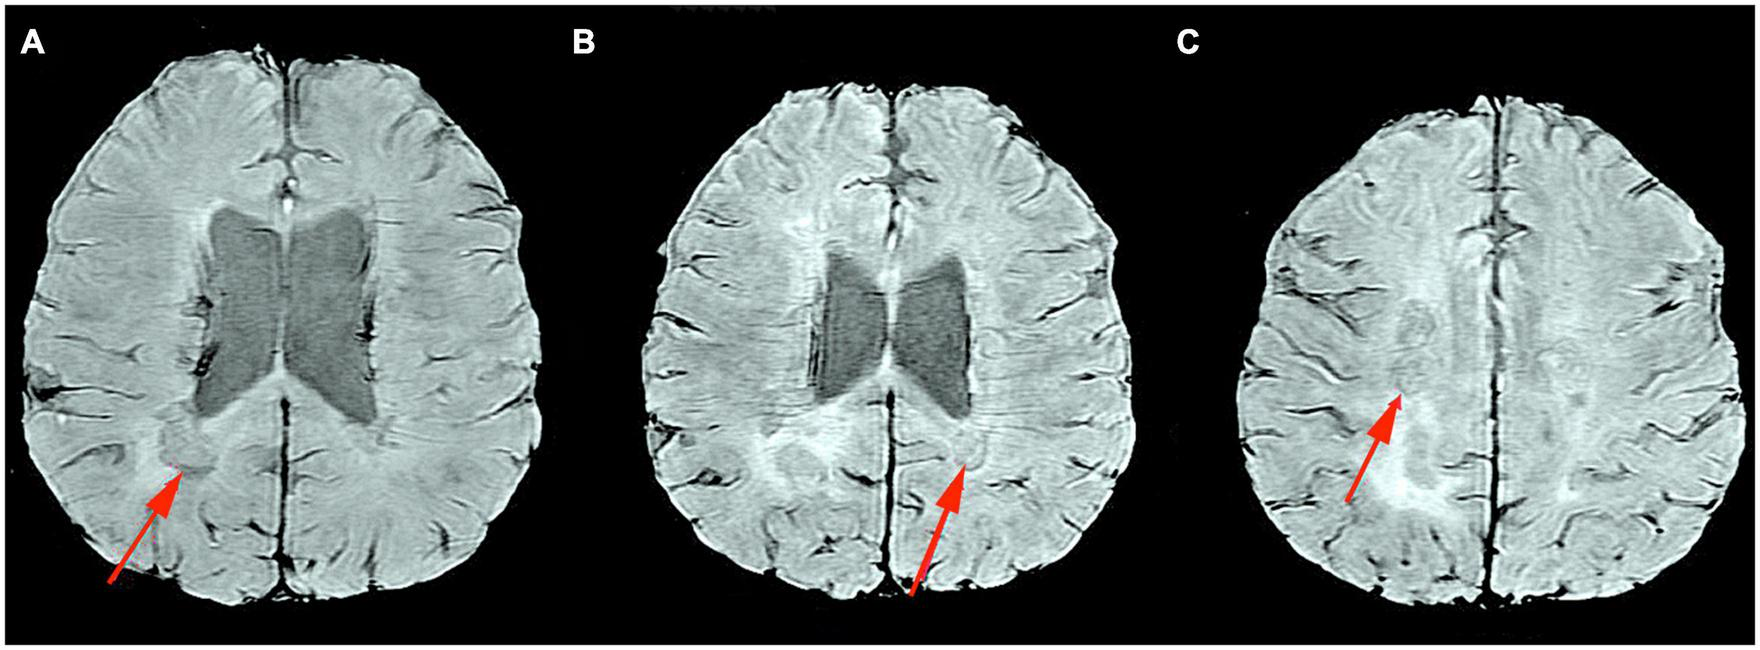

A comparison of the degree of brain atrophy and brain ventricular volume between a healthy control, a patient with RRMS, and a patient with SPMS is presented in Figure 1. All patients are under the care of the Neurological Clinic of the Military Medical Institute–National Research Institute.

FIGURE 1

MRI T2-weighted sequence, axial section. Comparison of the degree of brain atrophy and brain ventricular volume between healthy controls (A), patients with RRMS (B), and patients with SPMS (C). Material from the resources of the Medical Radiology Department of the Military Medical Institute–National Research Institute.